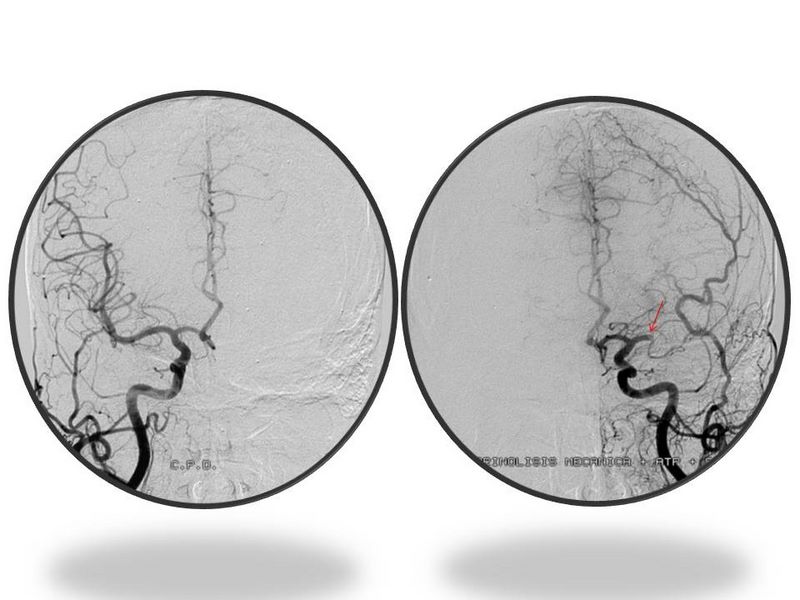

Ictus con stent